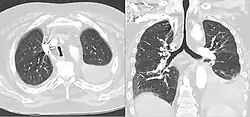

Saber-sheath trachea

A saber-sheath trachea also known as scabbard trachea is a trachea that has an abnormal shape. This manifests as a narrowing of the portion of the trachea located within the thorax, and a widening of the diameter of the posterior area of the trachea. The lateral measurement of tracheal diameter decreases. In saber-sheath trachea, the inner wall of the trachea is smooth, there are no nodules or areas of thickening.

On typical CT scans of the trachea, the normal appearance is oval, round, or horseshoe shaped. A saber-sheath trachea has distinct findings compared to normal tracheas on imaging, and may have additional features on CT besides intra-thoracic narrowing and widening diameter of the posterior portion. When cartilage becomes weak, as in saber-sheath trachea, CT scans can show the sides of the trachea curving inwards. This can be more apparent with forceful exhalation Moreover, the walls of the trachea within the thorax can also show slight thickening on CT. Another finding that can be seen is the hardening and becoming more bone-like of the cartilaginous rings in the trachea, a process called ossification.[5]